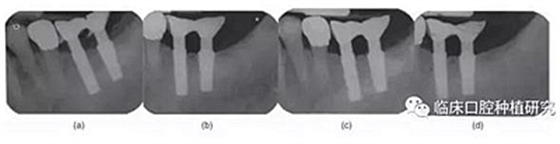

本研究的目的是評(píng)估種植體MicrothreadTM微螺紋結(jié)構(gòu)對(duì)維持種植體周邊緣骨水平的長(zhǎng)期效果的作用。通過對(duì)同一種植系統(tǒng)(Astra)的兩種種植體(Astra Tech Single Tooth:帶頸部微螺紋和AstraTech TiOblast:不帶微螺紋)的三年前瞻性觀察研究,發(fā)現(xiàn)頸部微螺紋設(shè)計(jì)有助于維持種植體邊緣骨水平穩(wěn)定。

但是MicrothreadTM微螺紋設(shè)計(jì)對(duì)牙槽骨水平的早期穩(wěn)定性的效果仍待證實(shí)。針對(duì)骨的機(jī)械性能的研究(Guo 2001)發(fā)現(xiàn)骨組織對(duì)壓應(yīng)力的抵抗力最強(qiáng),對(duì)牽張應(yīng)力的抵抗強(qiáng)度減少30%,對(duì)側(cè)向剪切力的抵抗力則減少65%。因此為了將骨吸收量降至最低,可以減少牙槽骨側(cè)向剪切力的種植體頸部設(shè)計(jì)是非常重要的。需要進(jìn)一步有關(guān)微螺紋和種植體其他設(shè)計(jì)元素的研究來明確種植體設(shè)計(jì)和牙槽骨吸收的關(guān)系和機(jī)制。